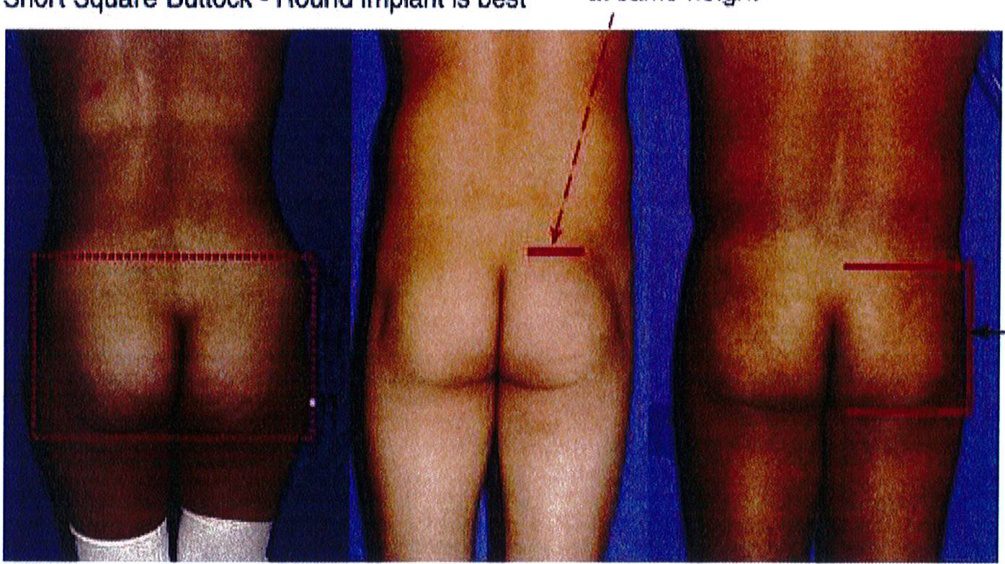

Short Square Buttock – Round implant is best

Short gluteus: height and width is the same (1:1 ratio)

Tall Square Buttock – Best to use an anatomic implant

Tall gluteus: the muscle is taller than it is wide (2:1 ratio)

ình. 8. Hình minh họa khung vuông, cao. Cơ mông lớn có tỉ lệ cao/rộng = ..

Dạng còn lại là dạng trung gian, nằm giữa dạng khung cao và khung thấp vừa mới đề cập ở trên. Cơ mông lớn có chiều cao/rộng = 1:1 hoặc 2:1. Mông dạng vuông thường được cải thiện tương đối nhiều khi hút mỡ điểm A và B. Điểm C có thể cần ghép mỡ, tùy thuộc vào mức độ lõm tại điểm này (Hình 9).

Hình dạng này độc đáo ở chỗ chúng có thể cao, trung bình hoặc ngắn (Hình 7 và 8). Để hiểu rõ khái niệm này, cần phải nhớ rằng khung bao gồm da, mỡ và xương. Khung xương chỉ hữu ích để xác định đây là khung cao, trung bình hay ngắn. Giới hạn trên của khung xương là đường viền trên của mào chậu. Nên tùy thuộc độ cao của chúng mà cơ mông lớn sẽ bám vào khung xương tại các vị trí khác nhau. Cụ thể, biến thể đầu tiên gắn đường viền trên cơ mông lớn dọc Theo đường viền trên của toàn bộ mào chậu, chúng để lại rất ít khoảng trống giữa bờ trên của cơ và mào chậu. Loại này hình thành khung chậu ngắn, tỉ lệ cao/rộng của khối cơ là 1:1. Dạng biến thể thứ hai, cơ bám thấp hơn trên khung chậu, sao cho mép trên của cơ cách mào chậu khoảng ½ chiều dài cơ. Loại này được gọi là khung chậu cao, cơ thường có tỉ lệ cao/rộng là 2:1 (Hình 8)

Xác định điểm trên cùng và dưới cùng của khối cơ Cũng như điểm sát cùng bên trong và bên ngoài. Từ đó xác định mối tương quan giữa chiều cao và chiều rộng (tỉ số cao/rộng). Thông thường chúng sẽ được chia thành 3 nhóm là ngắn/ thấp (tỉ số 1:1), cao (tỉ số 2:1) và trung gian (nằm giữa 2 tỉ số trên) (Xem hình 7 và 8). Một cơ mông lớn ‘lý tưởng’ sẽ thuộc nhóm trung gian, nhưng thường nghiêng về nhóm cao (2:1) (Xem hình 1A).

Trong các thủ thuật nâng mông bằng implant, tỉ lệ này rất quan trọng. Cơ mông thuộc nhóm ngắn (1:1) sẽ phù hợp với vật im- plant tròn vì cùng tỉ lệ, còn nhóm cao (tỉ 2:1) thì nên sử dụng ana- tomic implant (hình giọt nước). Còn cơ thuộc nhóm trung gian sẽ linh hoạt hơn và có thể dễ dàng im- plant với 1 trong 3 loại vật implant: tròn, anatomic, hoặc hình oval. Tuy nhiên, nên nhìn vùng mông từ phía bên để đưa ra quyết định cuối cùng về hình dạng vật implant (sẽ thảo luận sau).